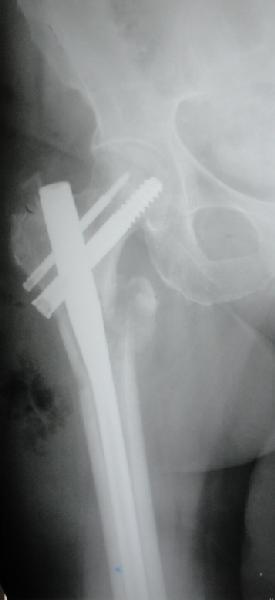

Re: Чрезвертельный перелом бедра

E> На мой взгляд, причиной телескопирования явилось несоответствие

E> диаметра гамма нэйл с диаметром канала подвертельного отдела бедра:

Диаметр гаммы в диафизарной части ~11 мм. А диаметр канала, тем более у пожилых с остеопорозом, может быть мм 15. Даже рассверливать обычно не приходится, после формирования широкого канала в вертельной области можно сразу толкать гвоздь, он влетает, как карандаш в стакан. Так что соответствия диаметров не бывает никогда. Однако представленная ситуация случается далеко не каждый раз. Если гвоздь в центральном отломке входит чуть медиальнее верхушки вертела, и идет вдоль передне-латеральной стенки центрального отломка, то все будет хорошо.

В приложении похожий пример, к счастью, пациентка появилась не после, а "за полчаса" до протрузии. Пересинтезировали с исправлением ошибок.